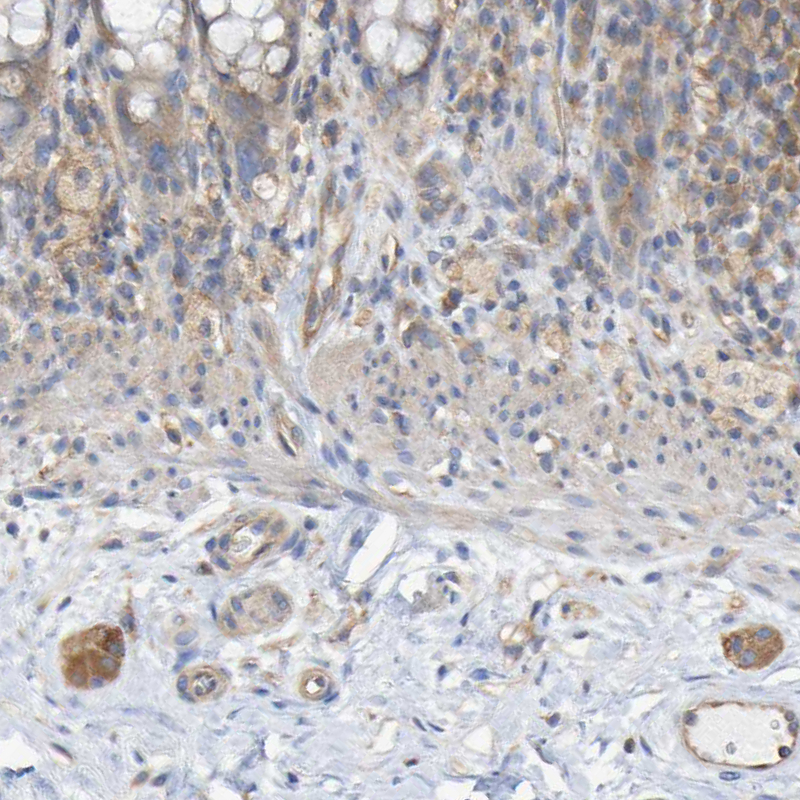

Immunohistochemical staining of human cerebellum shows moderate positivity in neuropil as well as in a subset of neurons.